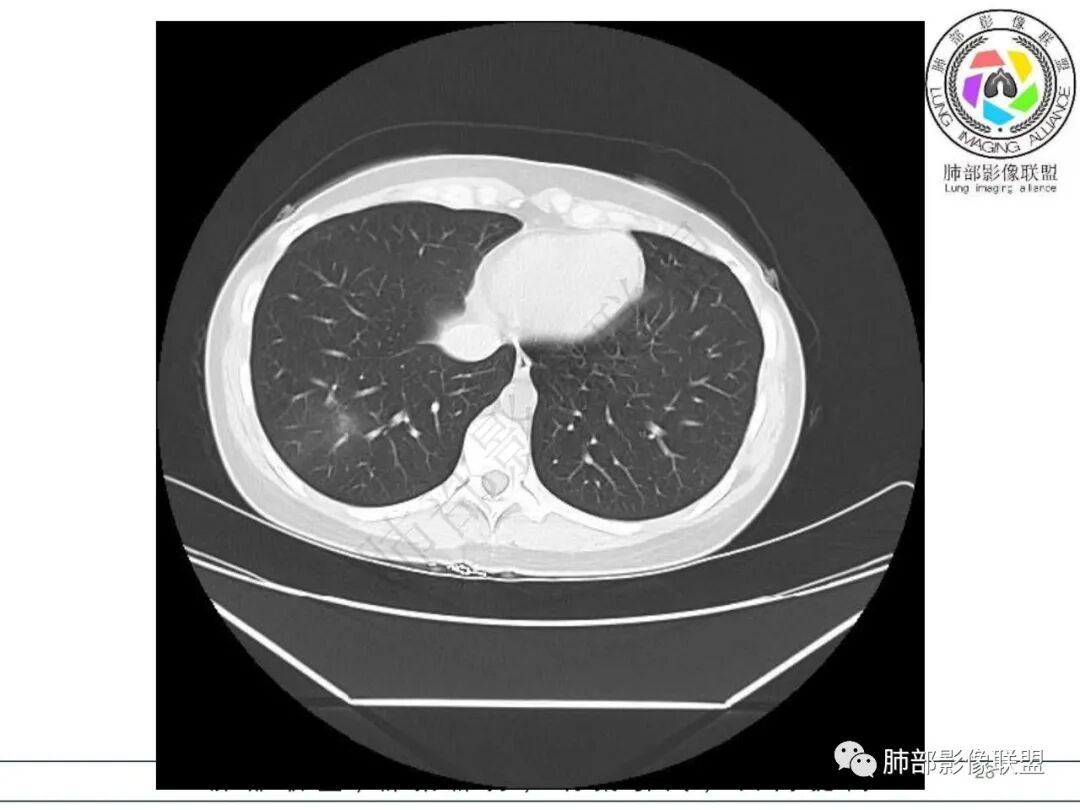

2.影像特征:右肺下叶局限性实变影伴晕征,边界不清,内部支气管尚通畅,实变区密实区边缘稍膨隆。符合炎性病灶特征。

右肺下叶局限性实变影伴晕征。

后、外基底段实变

周围GGO边界不清

内部支气管还算通畅

偏密实区支气管显示欠佳,密度稍低区支气管显示,密实区边缘稍膨隆